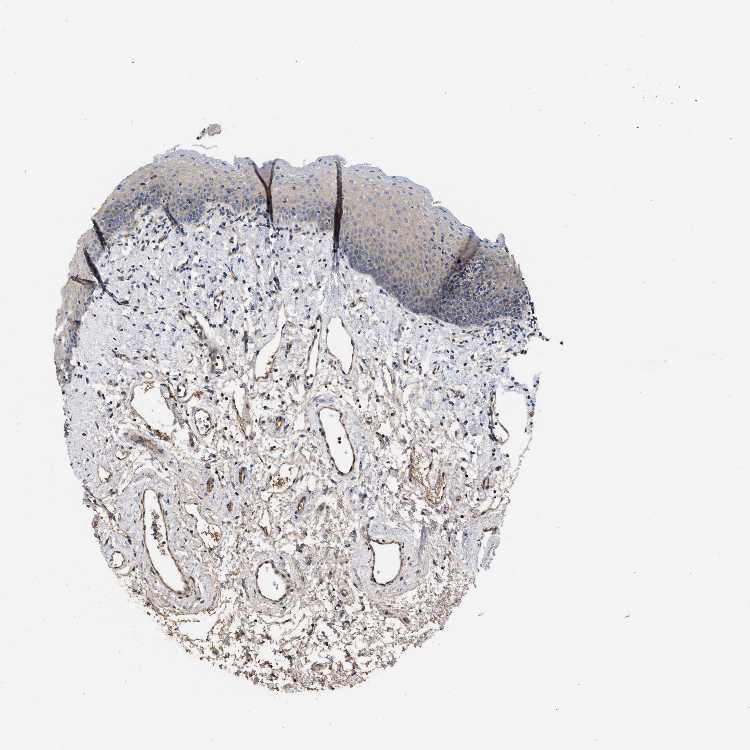

TISSUE PRIMARY DATA ORAL MUCOSA Show tissue menu

ORAL MUCOSA - Antibody stainingi

Antibody staining in the annotated cell types in the current human tissue is reported as not detected, low, medium, or high, based on conventional immunohistochemistry profiling in selected tissues. This score is based on the combination of the staining intensity and fraction of stained cells.

Each image is clickable and will lead to virtual microscopy that enables deeper exploration of all samples and also displays staining intensity scores, fraction scores and subcellular localization as well as patient and tissue information for each sample.

Antibody HPA018499

Squamous epithelial cells Low